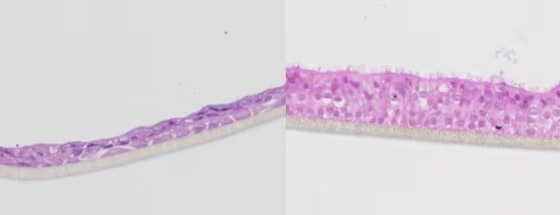

الرئتان اللتان يبلغ عرضهما بضعة ملليمترات فقط، تشبهان رئتي البشر بدرجة طفيفة. وهما موضوعتان في أنبوب بلاستيكي، وعند النظر إلى داخل هذا الأنبوب من أعلى، تبدوان مثل قطعة هلام صغيرة تنتشر في غشاء رقيق. حيث قال شرزانوفسكي: "من الضروري أن نتأكد من نمو الرئتين بما يكفي لتكونا جاهزتين وناضجتين للتجارب، لذلك طوّرنا أقطاباً كهربائية توضع باستمرار فوق نماذج الرئتين، وتراقب الإشارات الكهربية الحيوية لهما".

أُجريت محاولات أخرى لبناء رئات معملية، لكن شرزانوفسكي يقول إنها بسيطة جداً، وثابتة جداً، لكن رئة الإنسان تتغير وتتوسع وتتحرك باستمرار، بسبب تأثير الدورة الدموية وضربات القلب، على سبيل المثال. الفرق بين هذه النماذج البسيطة والرئتين اللتين صنعهما شرزانوفسكي، صاحب الفكرة، وتلميذته في الدكتوراه ثانه هوين فان، التي أسهمت بدور أساسي في تصميمها وبنائها، هو أنها تتضمن هذه الحركة الفسيولوجية للسوائل في الخلايا.

يقول شرزانوفسكي: "بدأنا في بناء هاتين الرئتين حرفياً خلية خلية، لنجعلها أقرب ما يمكن إلى فسيولوجية رئتي الإنسان. وهذا ما يجعل نموذجنا فريداً من نوعه. والميزة الأخرى لنموذجنا هي أنه يمكننا أخذ خلايا من مرضى مختلفين، وإضافتها إلى هاتين الرئتين لتجربة العلاجات المخصصة".